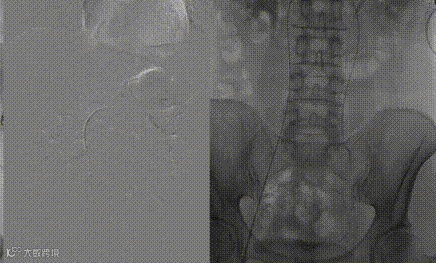

行左侧肾静脉造影显示:左肾静脉通畅,可见迂曲粗大的左侧卵巢静脉;

导丝单弯导管配合超选入左侧卵巢静脉,手推造影剂示:左侧卵巢静脉迂曲扩张,中到重度返流。

使用微导管到达卵巢静脉病变处,置入2枚18系统8mm*20cm中天完全可控外周弹簧圈,再次手推造影剂未见静脉返流。